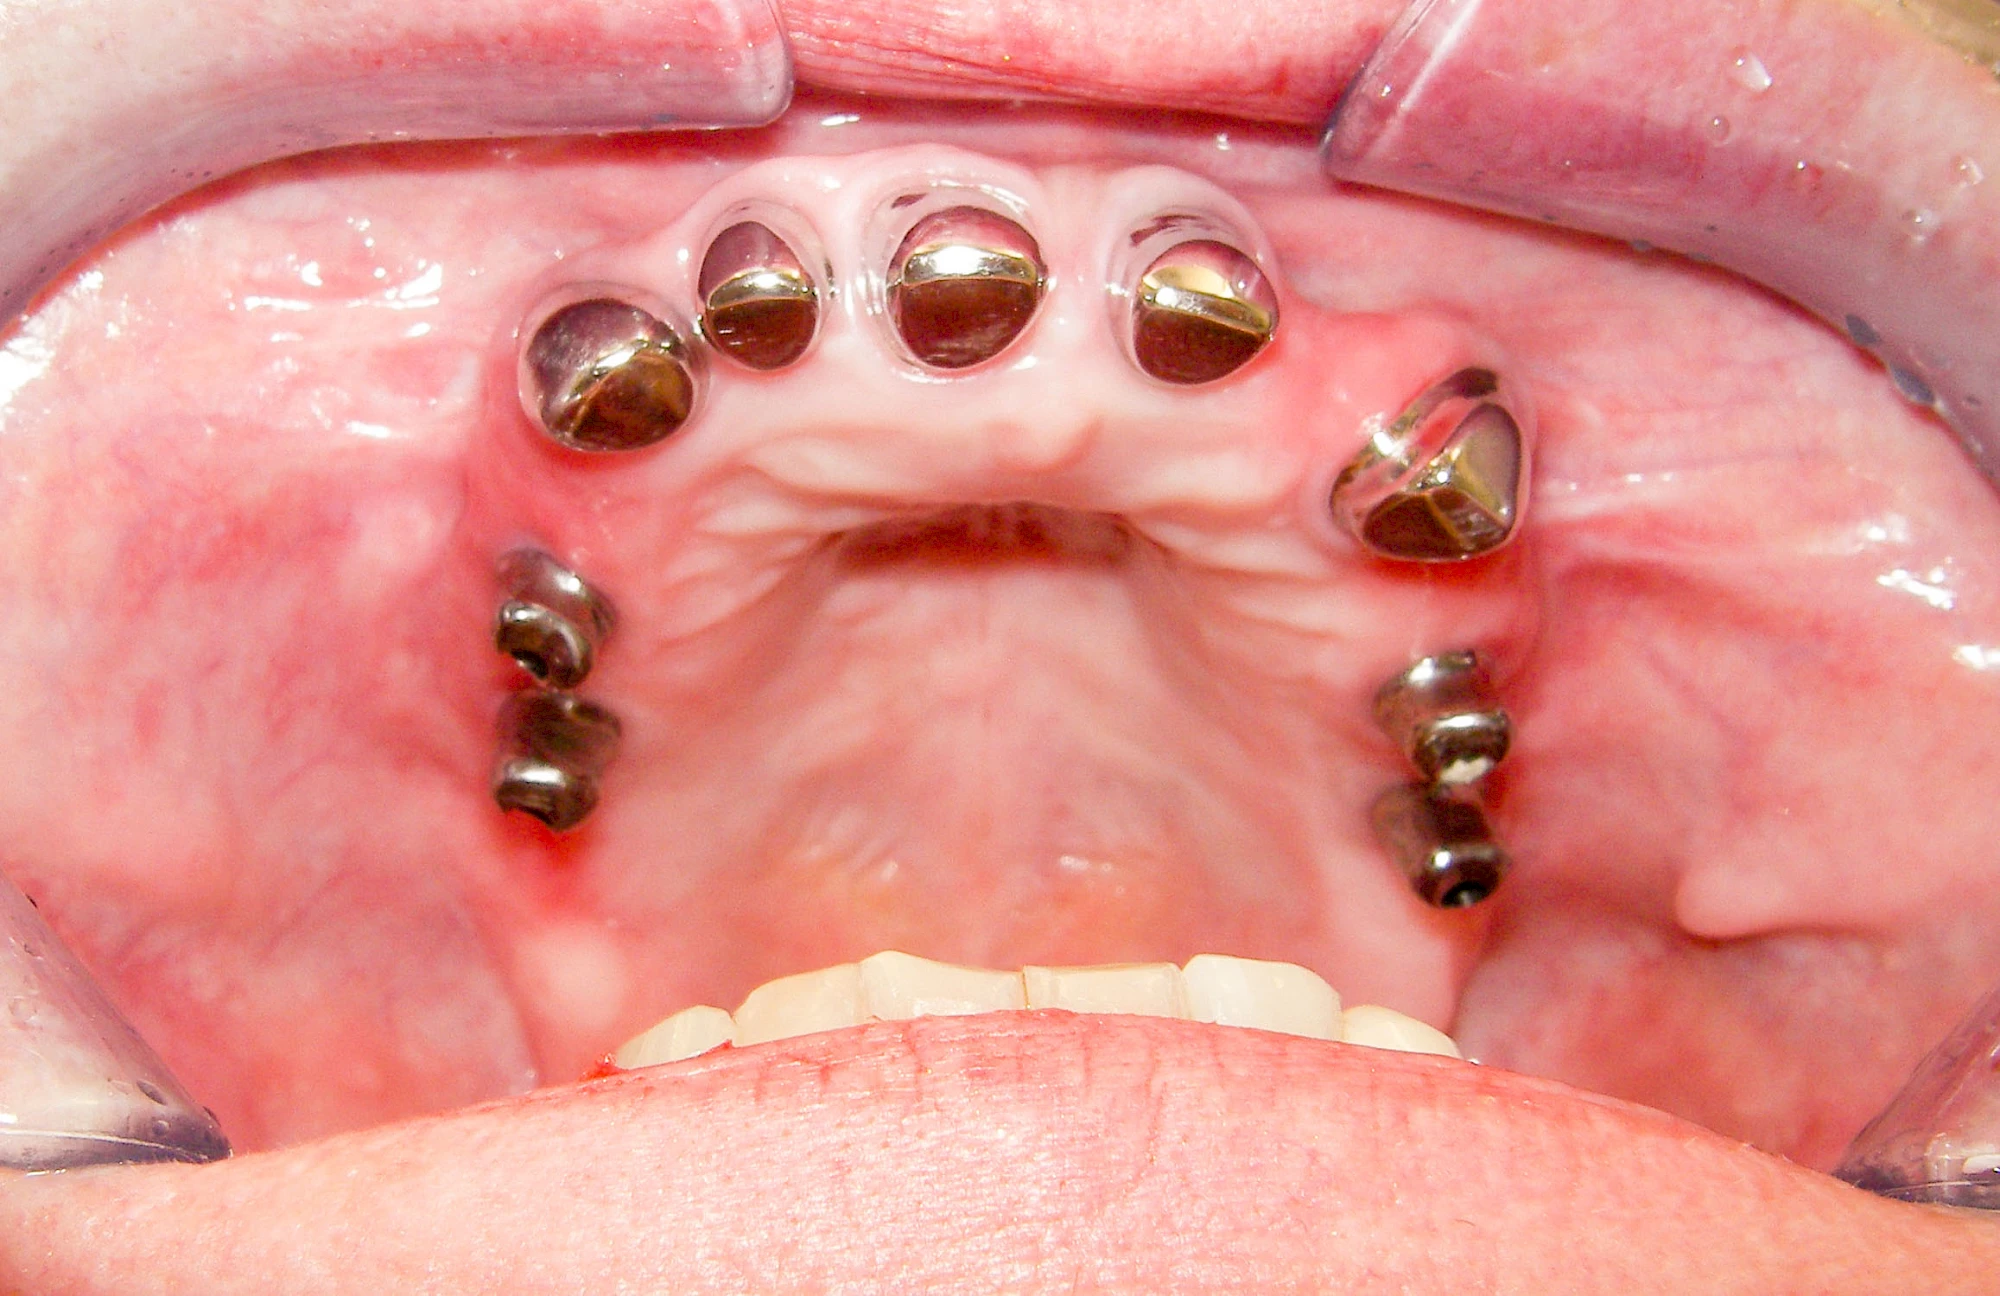

Implantate: Prothesen

Bei herausnehmbaren Prothesen werden Implantate eingesetzt, um den Halt und den Tragekomfort der Prothesen zu verbessern. Dazu kommen verschiedene Verbindungselemente zum Einsatz:

- Teleskope

- Kugelköpfe

- Tellerförmige Lokatoren

- Stege

- Magnete (selten)

Neben rein implantat-getragenen zahnärztlichen Versorgungen werden bei herausnehmbaren Prothesen Implantate auch in Sinne einer "strategischen Pfeilervermehrung" ergänzend zu eigenen Zähnen zur Verankerung eines Zahnersatzes genutzt.

Varianten zur Verankerung von abnehmbarem Zahnersatz auf Implantaten